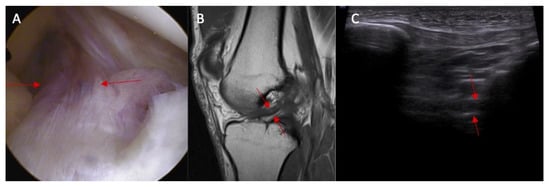

Swelling of the ACL intact to femur condyle was more common in patients with an ACL injury than in those without an ACL injury (83% vs. 0%, respectively, and p < 0.0001) (Figure 5). OR = incalculable.

Figure 5.

The proximal attached (marked with arrows) view of the ACL tear with edema. (A) arthroscopy view; (B) MRI view; and (C) ultrasound view—swelling of the ACL proximal attached to lateral femoral condyle.

Swelling of the ACL/PCL on ultrasound was more common in patients with an ACL injury than in those without an ACL injury (88% vs. 0%, respectively, and p < 0.0001) (Figure 6 and Figure 7). OR = incalculable.

Figure 6.

(A) Ultrasound view of swelling/scarifications of the ACL/PCL compartment with change of the morphology of the posterior joint capsule complex marked with the arrows and (B) normal view. PR—right.

Figure 7.

(A) ACL tear confirmed in arthroscopy view. Swelling of the ACL/PCL compartment with change of the morphology of the posterior joint capsule complex in (marked with red arrows) MRI view (B) and ultrasound view (C).